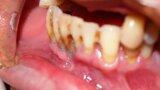

Implantacja z wykorzystaniem szablonu nawigacyjnego 3D